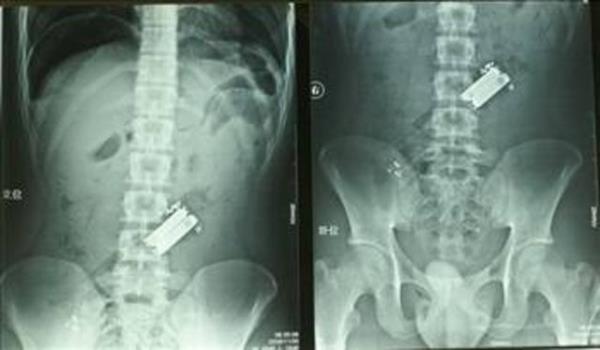

2. Aşırı alkollü genç hastaneye geldiğinde doktorlar neden bu kadar karın ağrısı çektiğini anlamadı... Ta ki genç yüz üstü yatıp da televizyon kanalı değişinceye kadar. 19 yaşındaki Huang Chen isimli genç, aşırı alkol aldıktan sonra kumandayı yutmuştu.

Aşırı alkollü genç hastaneye geldiğinde doktorlar neden bu kadar karın ağrısı çektiğini anlamadı... Ta ki genç yüz üstü yatıp da televizyon kanalı değişinceye kadar. 19 yaşındaki Huang Chen isimli genç, aşırı alkol aldıktan sonra kumandayı yutmuştu.